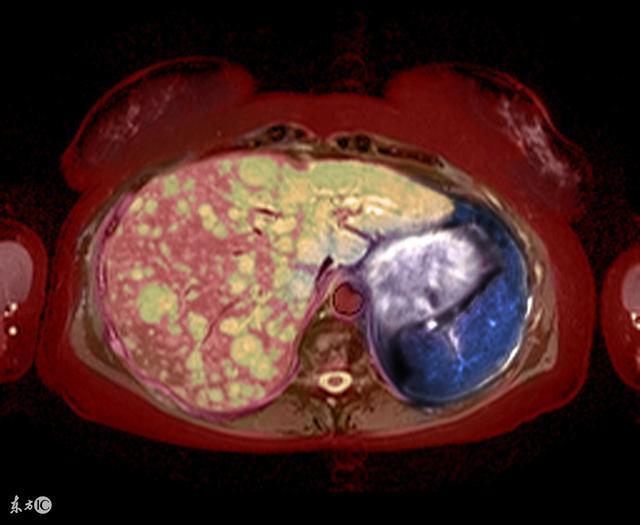

肝臟疾病的危害並不只限於肝臟,會表現在很多部位。比如皮膚,眼睛等。如果肝臟不好,還會影響到身體色素沉積,某些身體部位會發黑。一般來說,肝臟不好、有肝炎疾病的人,三個部位的色素沉積會更為明顯。

而當肝臟的本色出現在麵部時,則說明患者的肝臟病變比較嚴重。西醫解釋是肝病導致雌激素的滅活能力下降,色素代謝異常導致色素在皮膚沉積引起。正因為如此,臨床上的確有相當多的肝硬化患者,隨著病情的日益加重,臉色會變得越來越黑或越來越青。

很遺憾,如果出現2個部位疼痛,你可能患了嚴重肝病!我們知道,肝臟是最為沉默寡言的器官,被損傷後不會第一時間發出信號,這也是為什麼很多人無法及時發現肝病的原因。美國《預防》雜誌網站指出,肝功能減退會有7個徵兆,如果出現了以下癥狀,請儘快到醫院做進一步檢查和診斷。

腹部右上部感到疼痛、腫脹,是肝臟正處於危險的一個表現。

肝臟跨越大部分腹腔,形狀像個楔子,它的脂肪端在腹部右側。

3、眼睛或皮膚髮黃(黃疸)肝臟有處理廢棄血細胞的功能,併產生膽紅素。

若肝功能衰退,膽紅素就會堆積在血液中,使眼睛、皮膚都變黃。